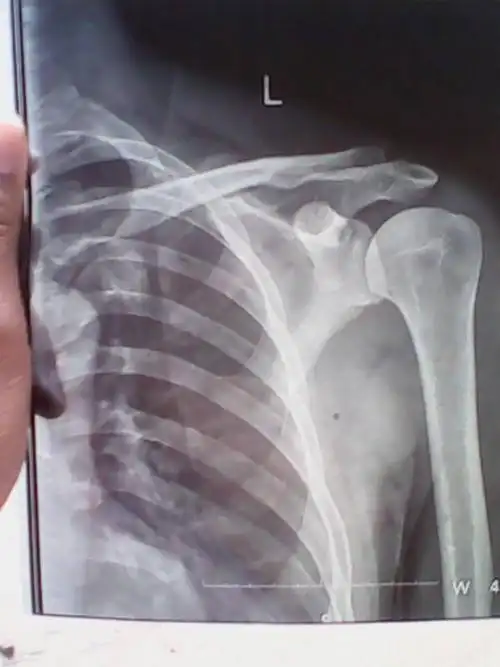

左肩锁关节脱位

肩锁关节脱位